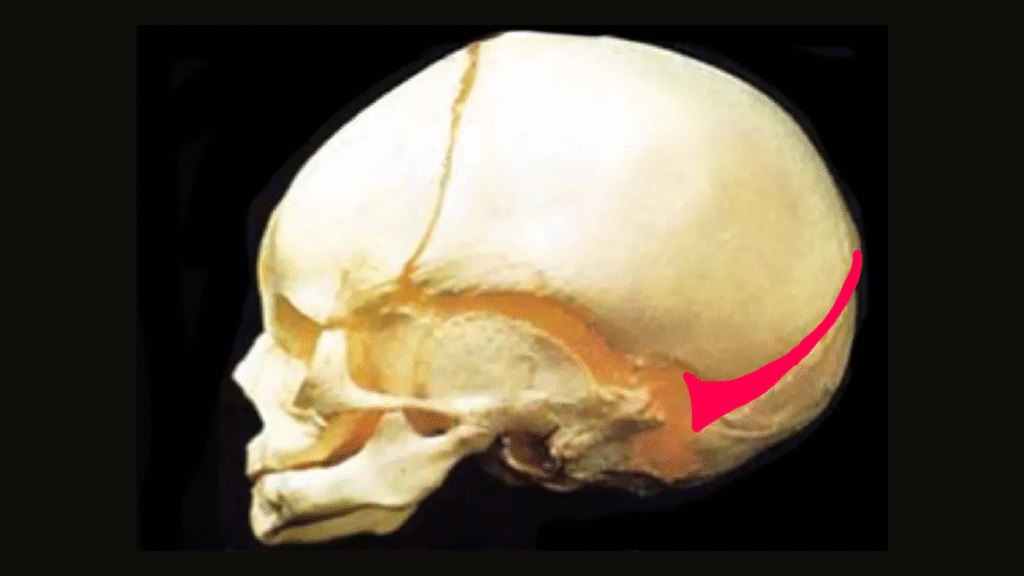

At El Paso Craniofacial Team, the primary treatment for craniosynostosis is surgery. First performed in the late 1800s, surgical approaches have continued to evolve and improve. The two main approaches are Calvarial Vault Remodel (CVR) and endoscopic-assisted surgery, with each tailored to the child’s age, the affected suture, and the severity of the condition.